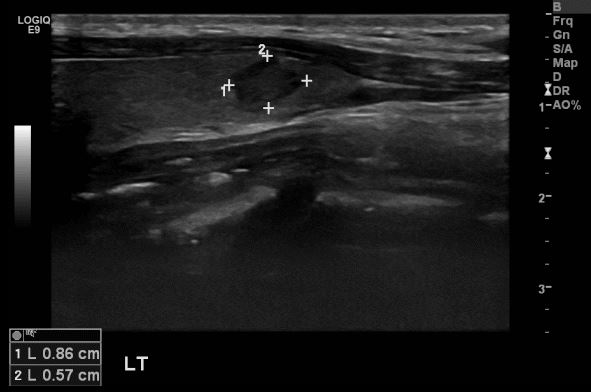

상기환자 목의 이물감으로 내원하신 40대 여성분으로 본원 초음파상 좌측 갑상선의

의심스러운 멍울 조직검사 시행하여 좌측 갑상선 유관암 진단 되었습니다.